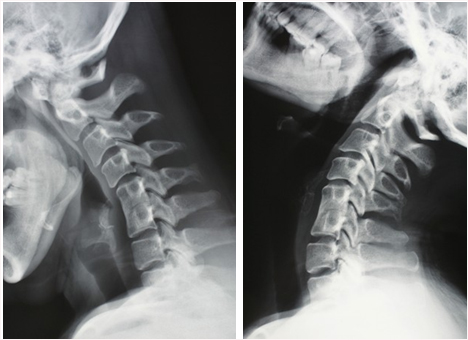

原本颈椎的正常生理曲度在俯卧撑姿势下是略微向地面有些凹陷,与腰椎的曲度方向相同,合理的运动范围是可以的,颈椎由于它的独特性虽然与腰围曲度方向相同,但是它的活动范围更大,就更容易出现在过度的伸展状态下,颈椎后方的棘突则会有可能出现挤压,这是由于颈部神经较多,则很有可能受到压迫

过度低头的状态与我们平时玩手机的状态相似但是更为严重,幅度更大,尤其是在运动过程中相关肌肉力竭之后的借力,就更容易使颈椎受到伤害,出现生理曲度变直